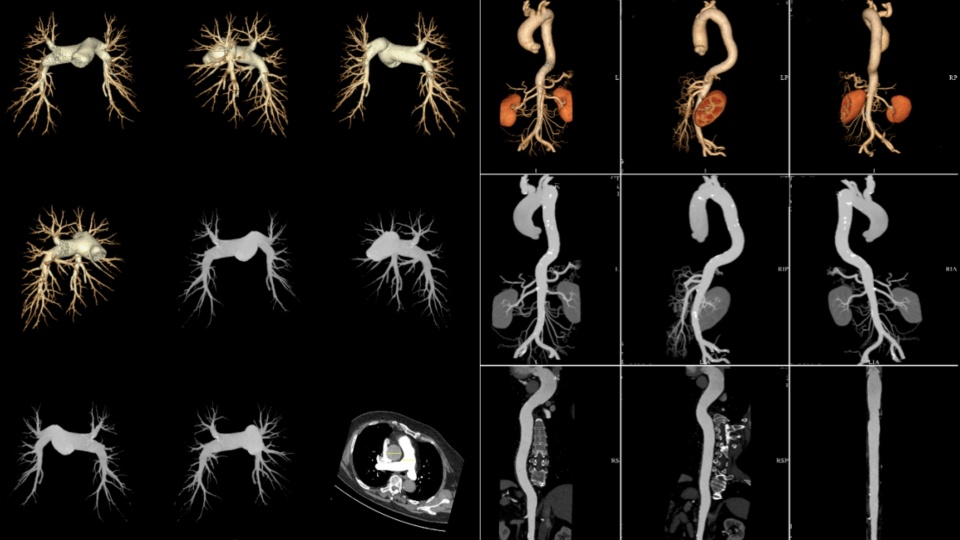

【渭南市第一医院影像科】心脏冠脉cta~2018.10.9病例展示

图片尺寸2122x1999